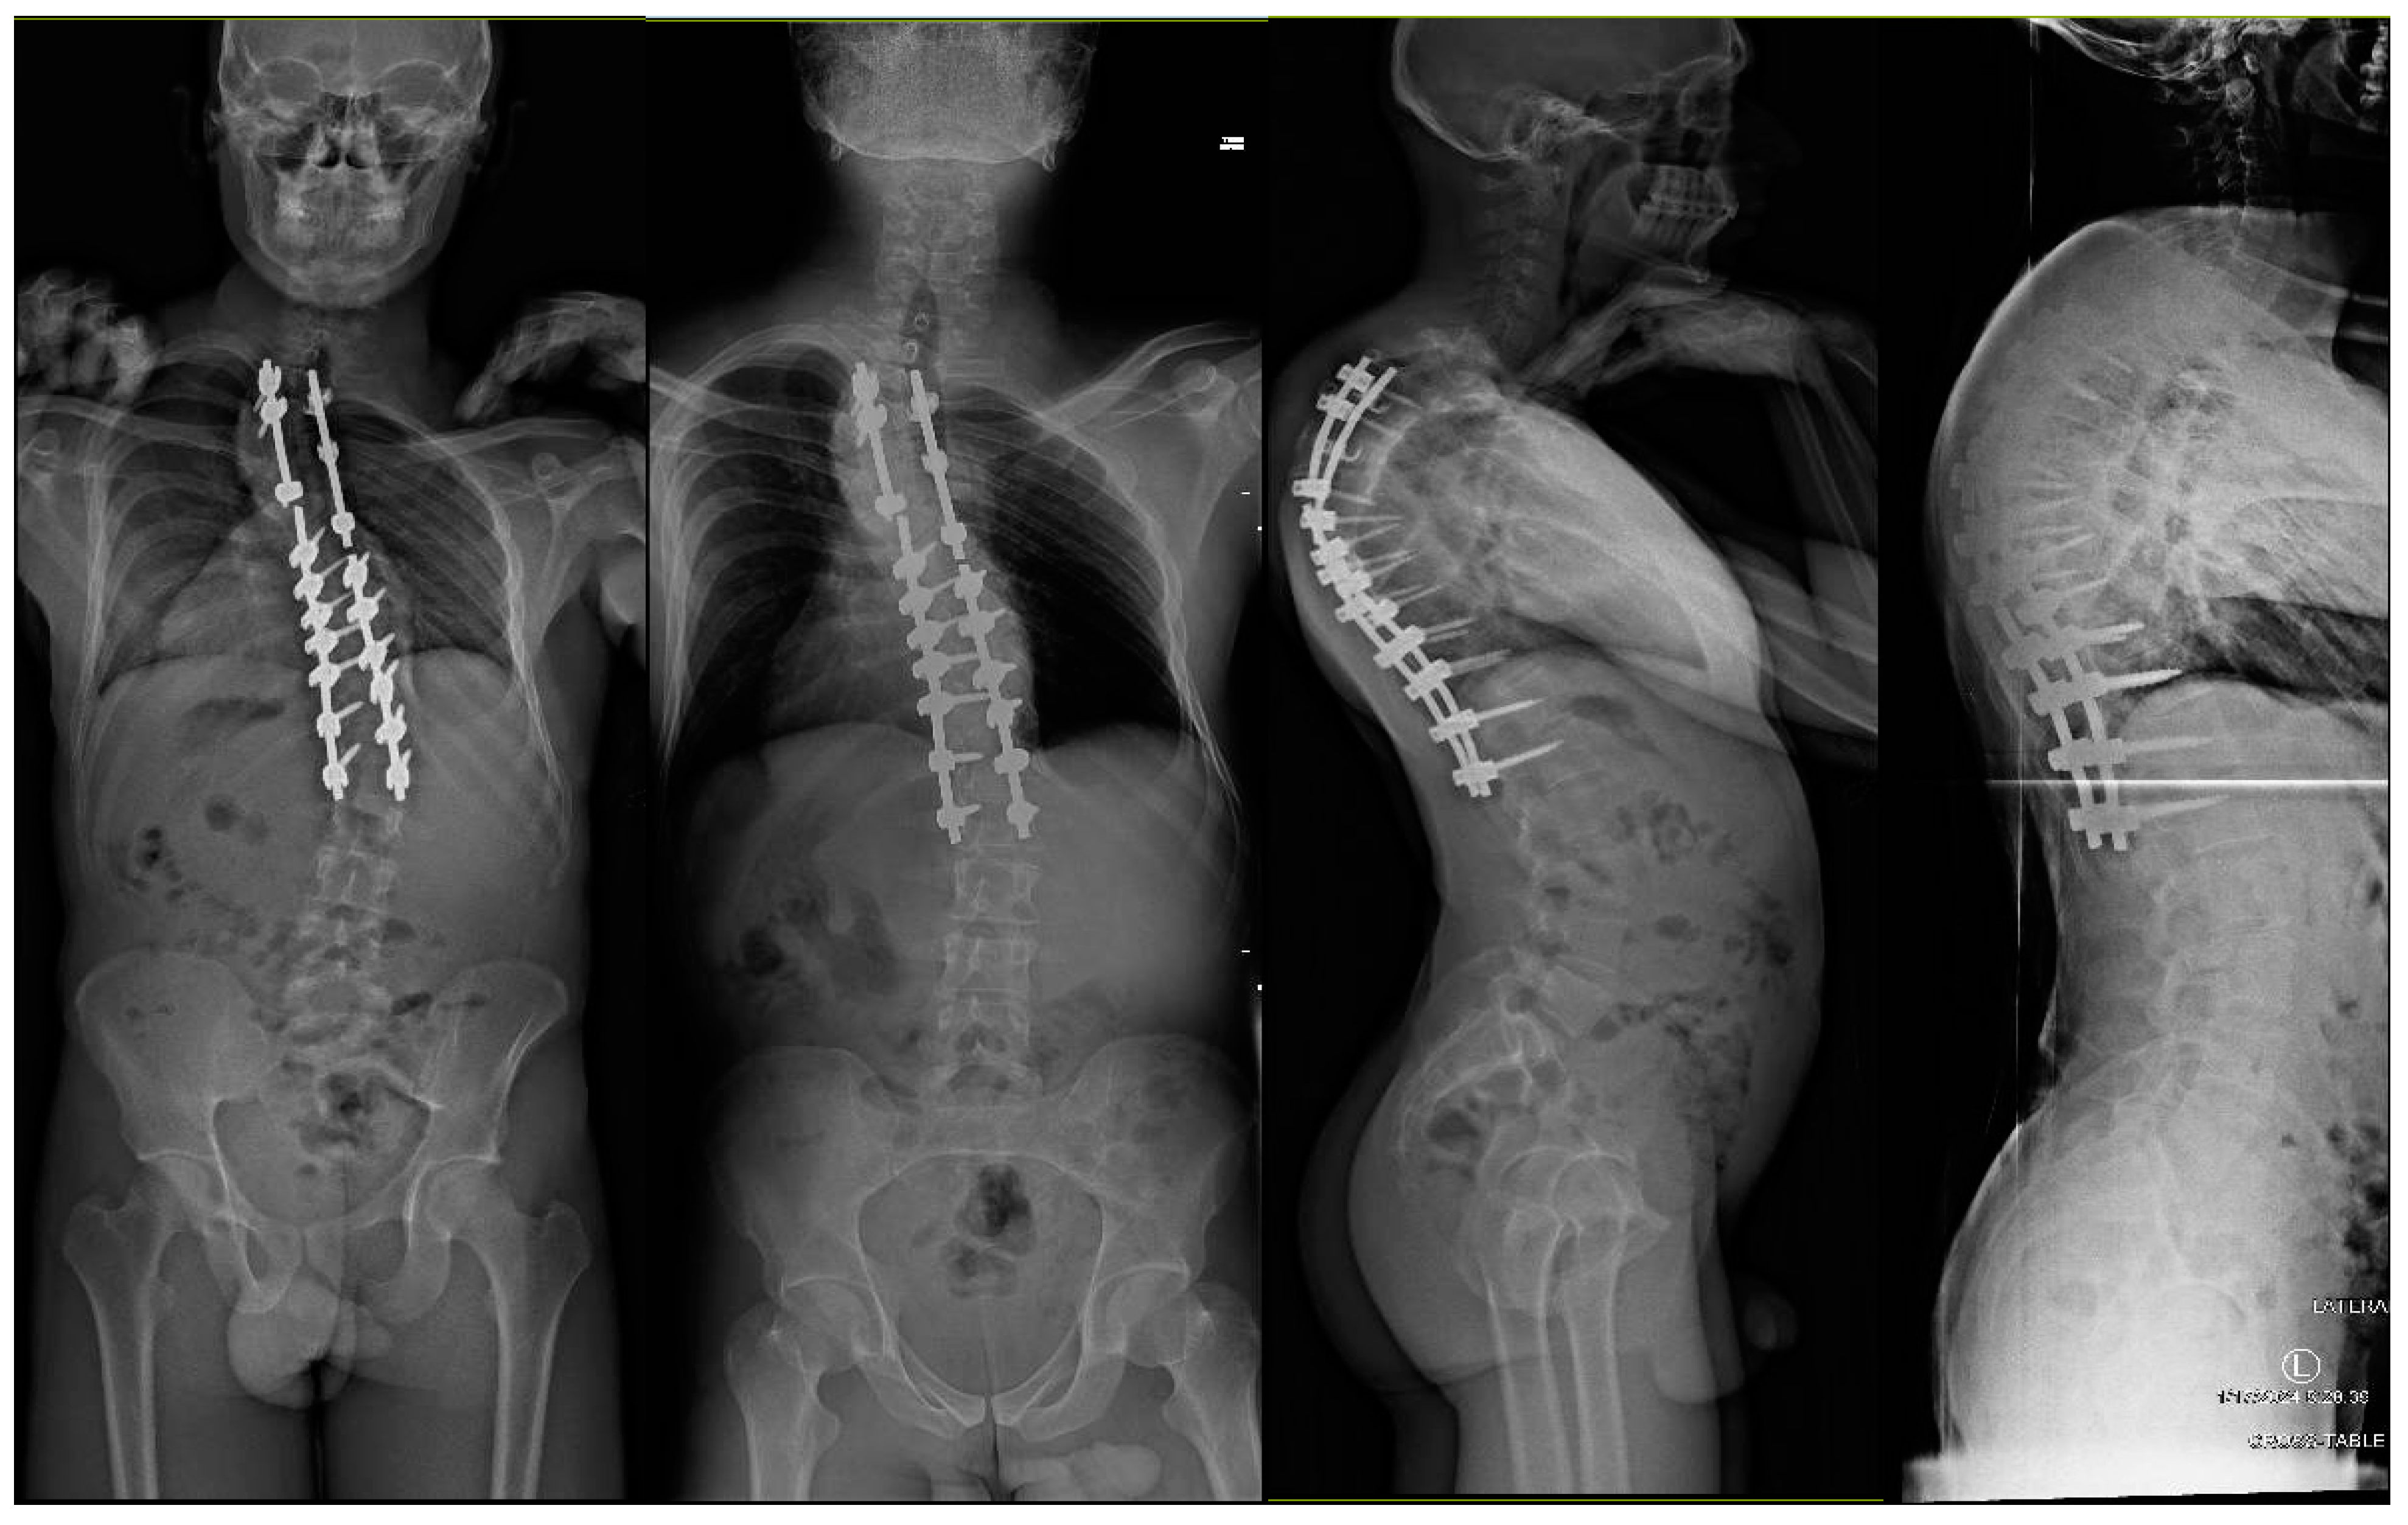

2. Case Discussions